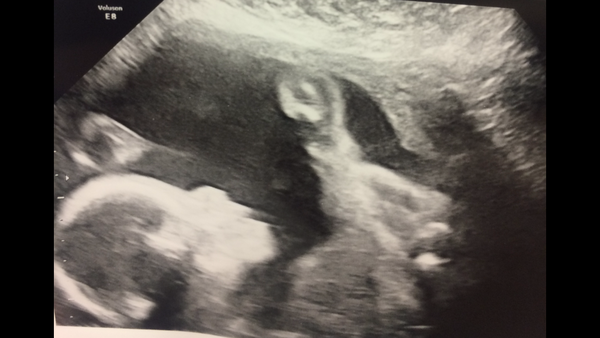

Bubs almost 25w. Finally moved and on her back and legs over her shoulders. With Right hand holding right leg

blondes what a lovely picture! I always like the ones where they're pulling random poses with their body parts... it makes me imagine they are going "woahhhhh what is this... what will it do if I do this..." Xmas Smile Xmas Grin Xmas Wink

Blondes how exciting to see your little one. Good clear scan picture too!

Blondes, that's a great scan picture, so clear!